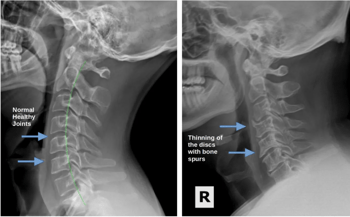

Back Pain